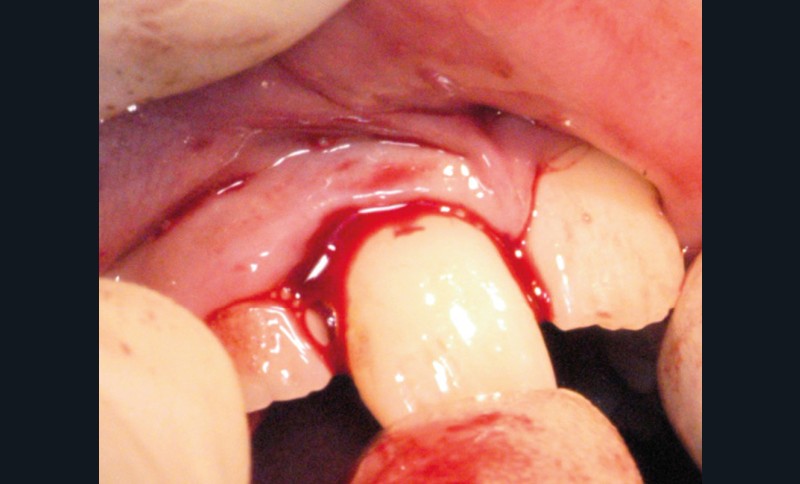

Enfant de 9 ans dont une incisive centrale maxillaire a été expulsée en jouant au football. Appel immédiat de la mère à qui l’on conseille de conserver la dent expulsée dans du sérum physiologique (fig. 1). Le temps extra-alvéolaire à sec a été inférieur à 5 minutes. Le patient arrive 40 minutes après le traumatisme dans l’Unité d’Odontologie pédiatrique. Après interrogatoire, examen clinique et radiographique, un rinçage de l’alvéole est effectué et la dent est réimplantée le plus rapidement possible (fig. 2). Une contention semi-rigide est ensuite placée (fig. 2). La dent étant mature, la prise en charge endodontique (séance de Ca(OH)2 puis obturation à la gutta percha) débute deux semaines plus tard (fig. 3 et 4) afin de limiter les risques d’infection, de résorption. Le suivi sur quatre années montre une dent fonctionnelle, sans ankylose ni résorption radiculaire ou osseuse.